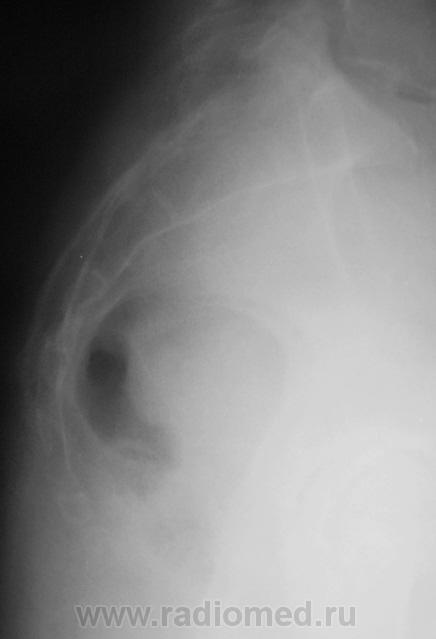

Пациент направлен на рентгенографию крестца и копчика с диагнозом "Перелом".

Похоже на перелом S4. Я, конечно, не поверю, что Вы обошлись только боковой. Опять интрига?

Нет никакой интриги. Просто снимок, произведенный в одной боковой проекции (не у нас) был дан для описания.

Если смотреть по задней пов-ти - то все ровно. Но я думаю, что нужно смотреть все-таки по передней, а там есть ступенька в S4. И если была травма и есть клиника - грех не поставить перелом. Хотя это настолько банально, что, я думаю, Вы бы его не выставили.